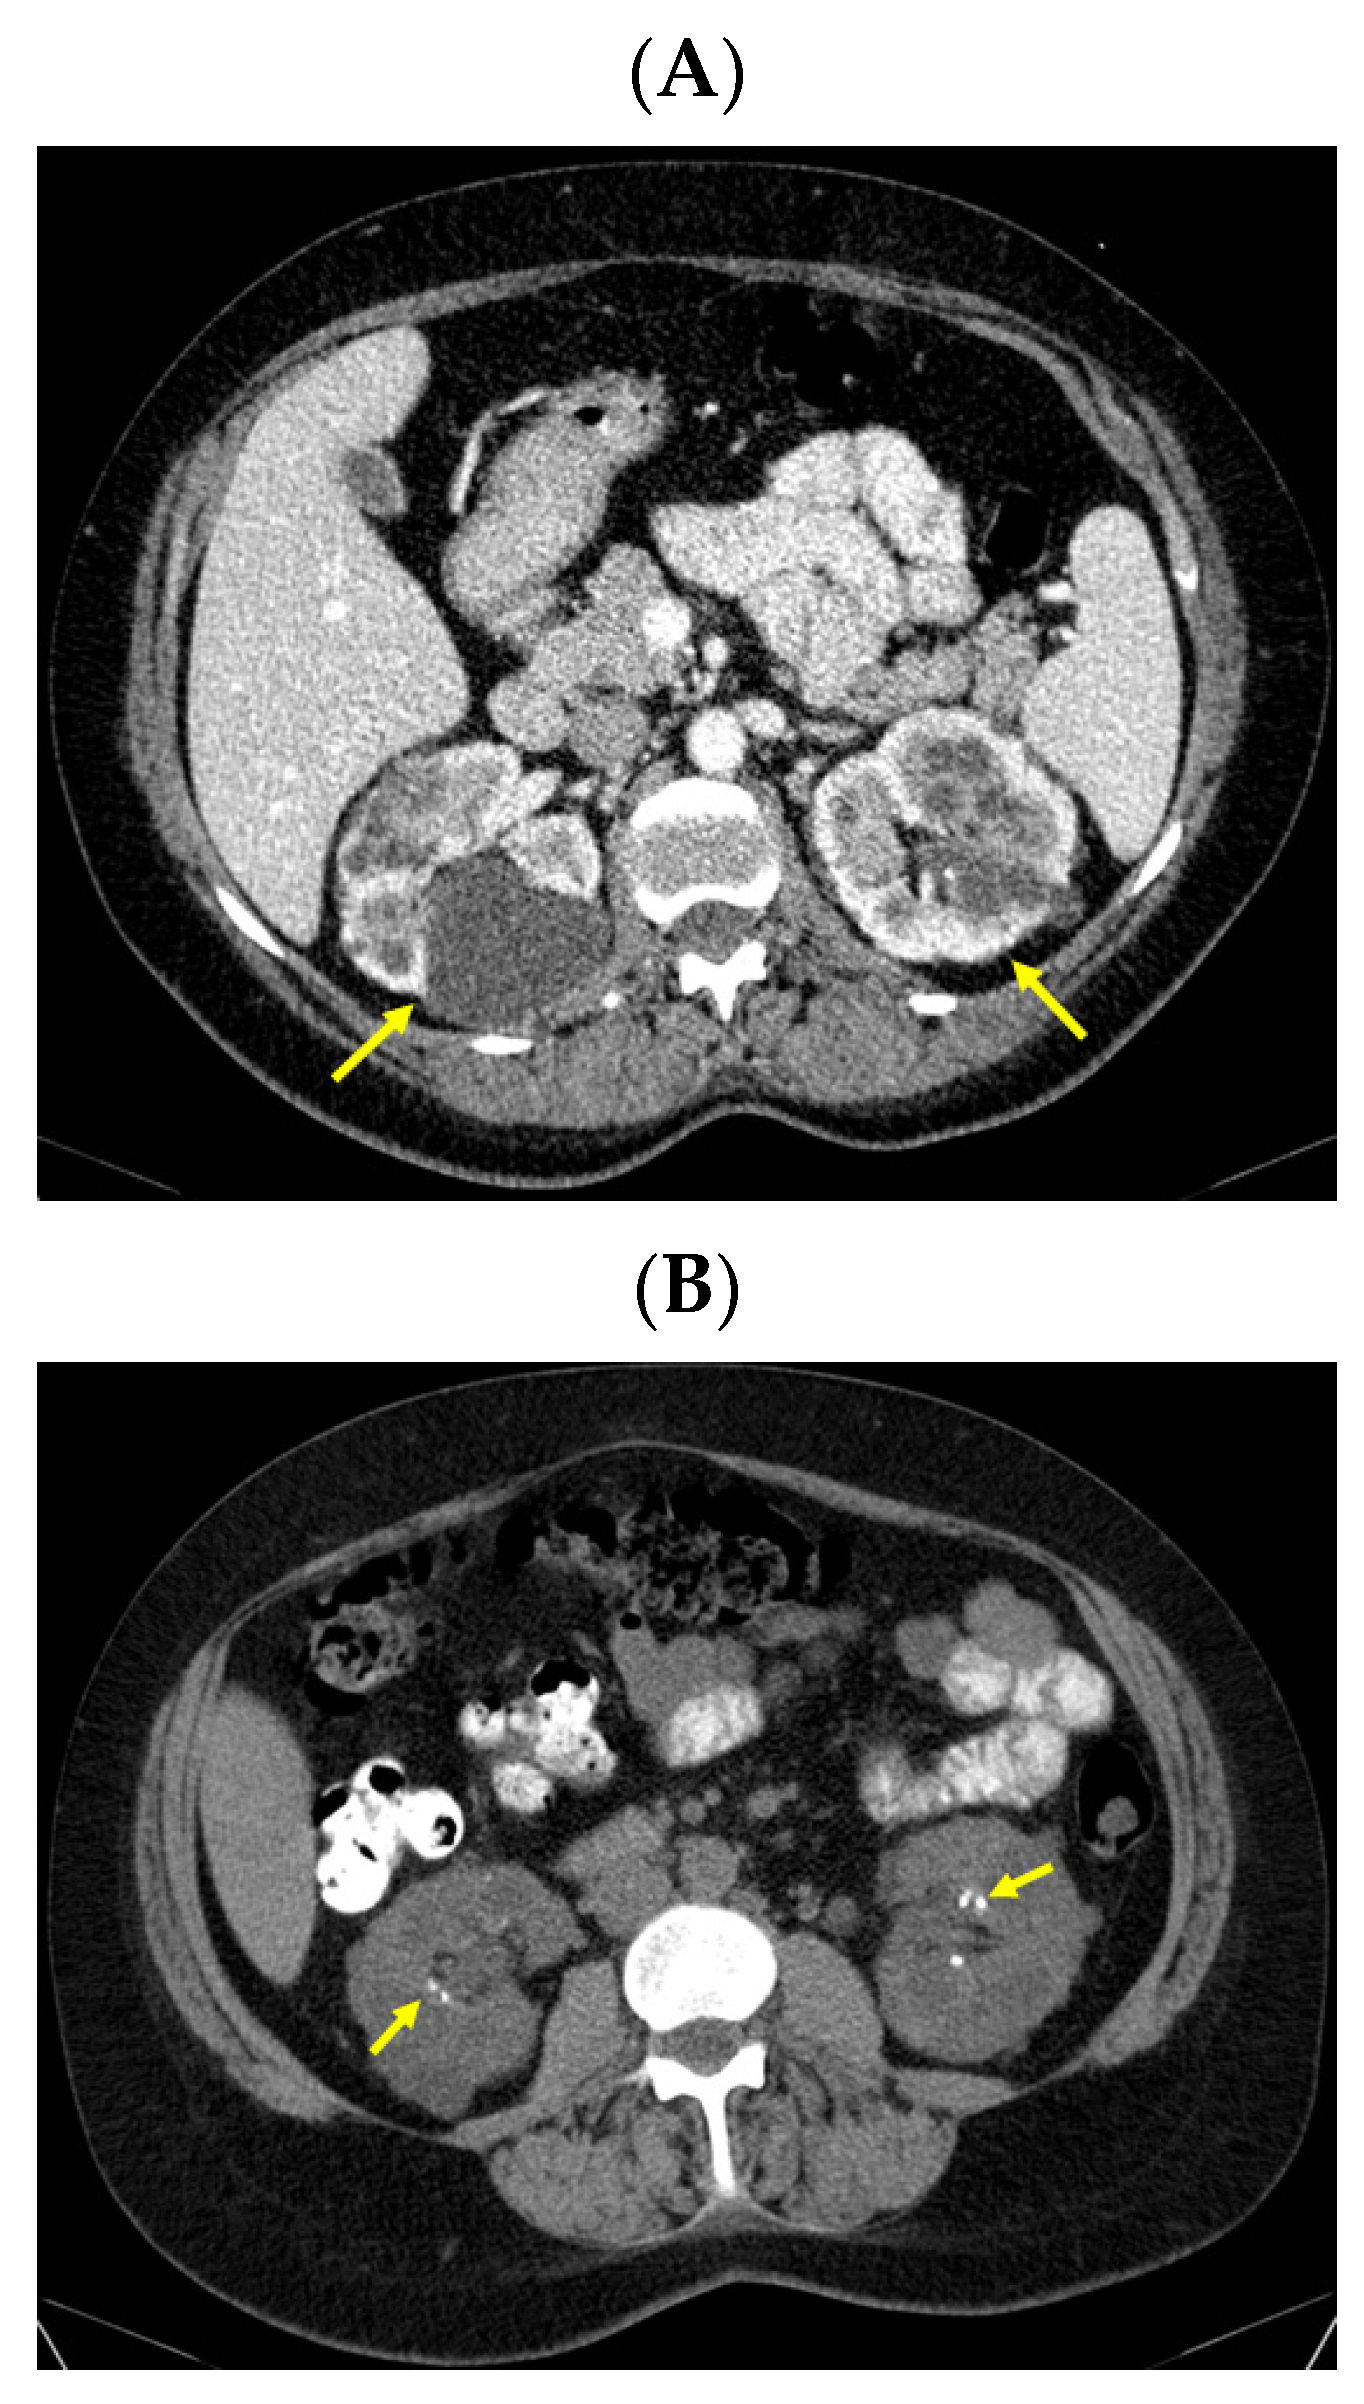

Moreover, an abdominal CT confirmed the bilateral polycystic features of the kidneys (with a convex contour due to multiple cystic lesions that were located in and protruding from the renal cortex; the posterior part of the right kidney contained the largest cyst of 6.27 by 5.36 by 6.01 cm with mass effect on the phyllo-caliceal system and protruding from the kidney). Of note, renal microlithiasis was co-present in both kidneys (Figure 8).

Figure 8.

Intravenous contrast abdominal CT showing: (A) both kidneys with multiple cystic lesions both located in and protruding from the renal cortex bilaterally, the posterior part of the right kidney with a cyst of 6.27 by 5.36 by 6.01 cm with mass effect on the phyllo-caliceal system and protruding from the kidney (the yellow arrows show cystic kidney disease) and (B) bilateral renal microstones in primary hyperparathyroidism in yellow (axial plane).